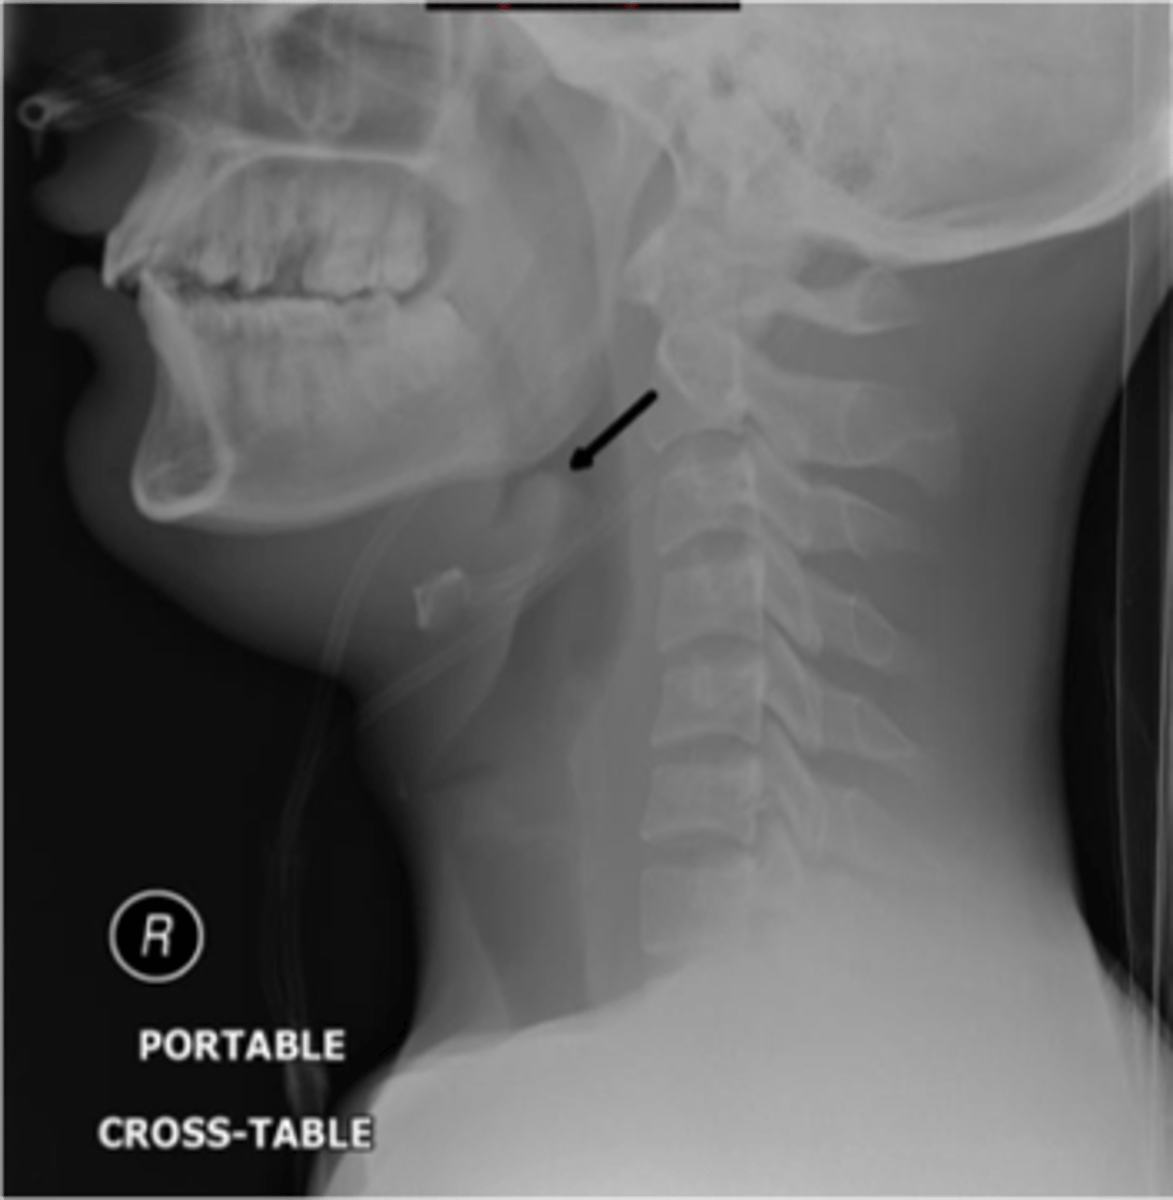

Epiglottitis (thumb sign)

knowt flashcard image